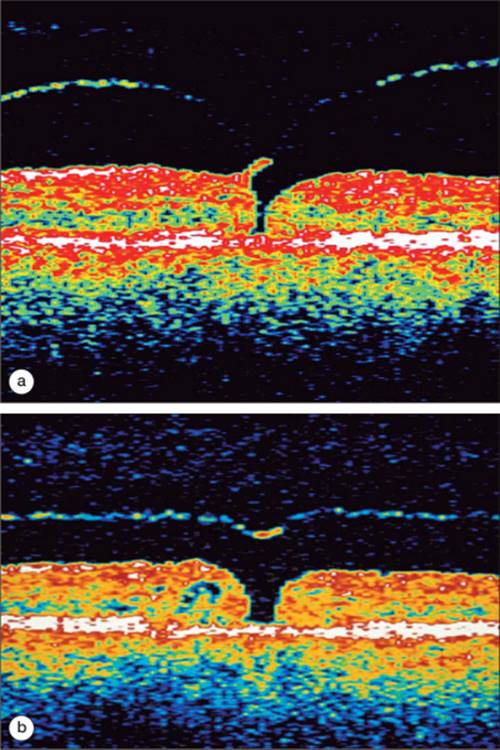

Figure 130.8 demonstrates a case of VMT traction. This is a series of OCT images taken from the same patient over the course of 13 months. Notice the thin band representing the posterior hyaloid which is inserting onto the surface of the retina. The retina displays cystic changes and there can be subretinal and sub-RPE fluid as well. There is obvious distortion of normal foveal anatomy in the later images.

Click to view full size figure

FIGURE 130.8 (a-c) This series of figures demonstrates a case of VMT that progressed over the course of 13 months. The patient complained of increasingly distorted and decreased vision.